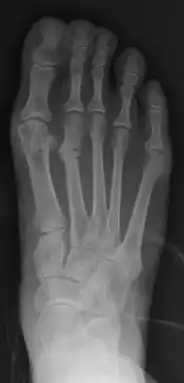

| Stress fracture of the second metatarsal bone (below the knuckles of the second toe) | |